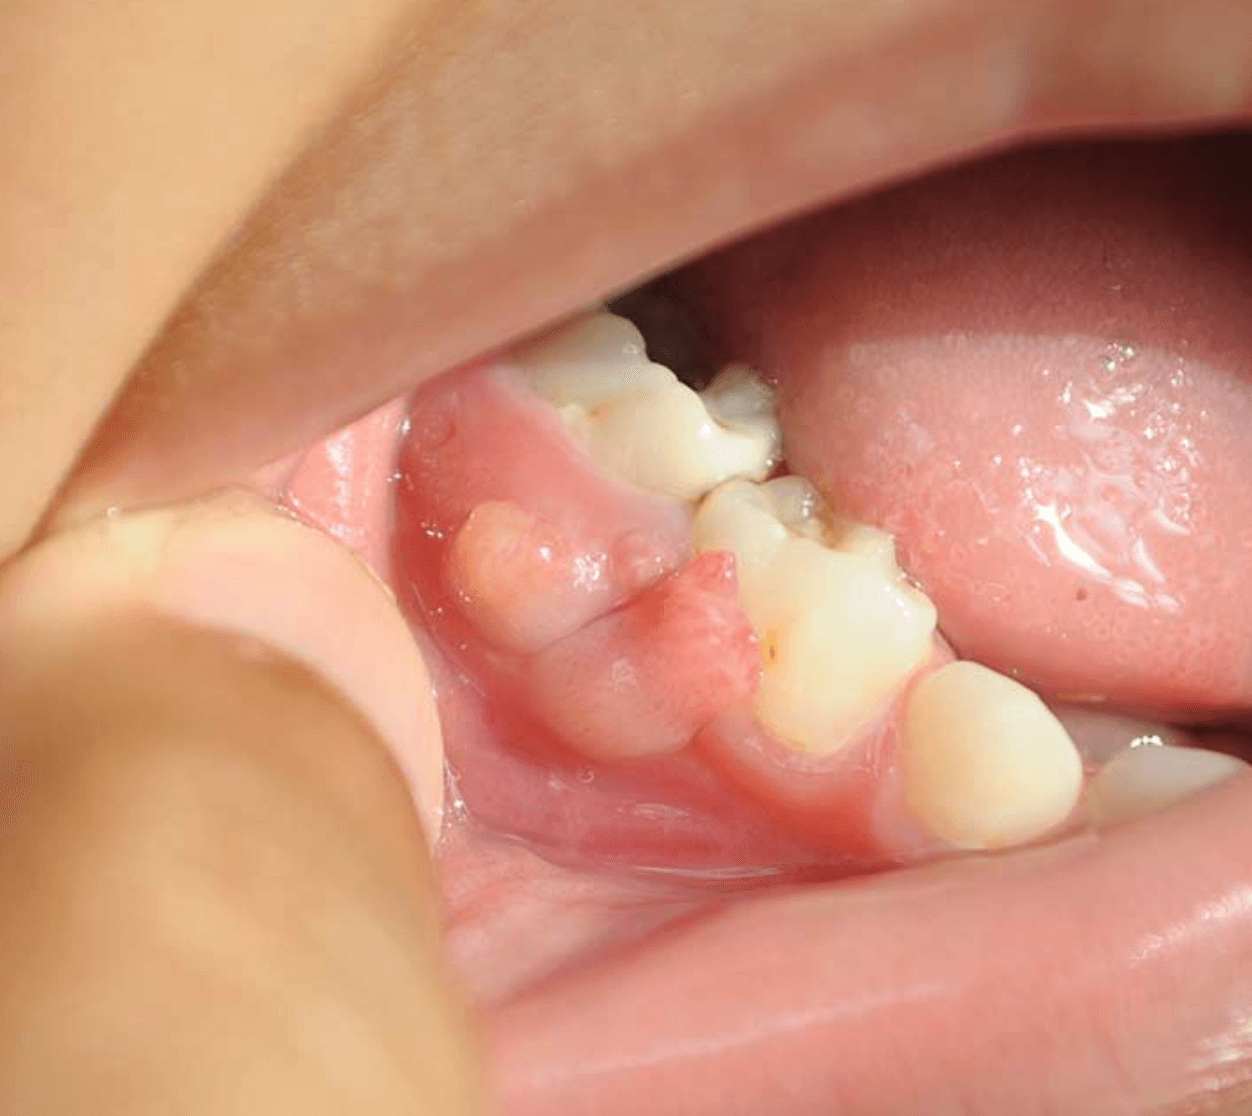

잇몸에 염증이 생기면 빠져나가지 못하는 고름으로 인해 잇몸이 푸불어 오르면서 고름 주머니가 생기게 됩니다. 이때 빠져나가지 못하는 염증은 주변의 살과 뼈를 녹여 아픈통증을 유발하지만 이러한 압력이 빠지게 되어 염증이 배출되면 통증은 사라져 괜찮은줄 알고 치과에 오지 않습니다.

이러기를 여러번 반복하다보면, 치아 뿌리 안으로 염증이 심각하게 고이게 되어 빠르게 치과에 오시는 분들은 신경치료를 통해 염증을 잡고 치료를 할수 있지만, 오래되어서 주변의 뼈를 다 녹여 문제가 심각한 경우 치아를 발치하게 됩니다.

대부분의 사람들은 이러한 신경치료를 통해 잇몸 염증을 치료할수 있습니다. 그러나 또다시 치아 뿌리에 염증이 생겨 잇몸에 고름주머니가 생기는 경우 재신경치료 또는 치근단절제술을 통해 잇몸을 절개후 염증 고름을 제거할수 있습니다.

염증이 광범위하거나 치근단절재술로도 염증을 잡을수 없을때 치아를 발치하게 되고 치료후 임플란트를 해야할수도 있습니다. 글쓴이가 이런경우로 현재 임플란트를 염증때문에 3개를 해넣고 현재 앞니 또한 치근단절재술로 뼈이식 까지 한후 치료를 다했지만 최근 잇몸에 다시 고름주머니가 생겨, 염증재발로 한번더 잇몸을 절개하고 치료를 할지 발치를 할지 고민중에 있습니다.